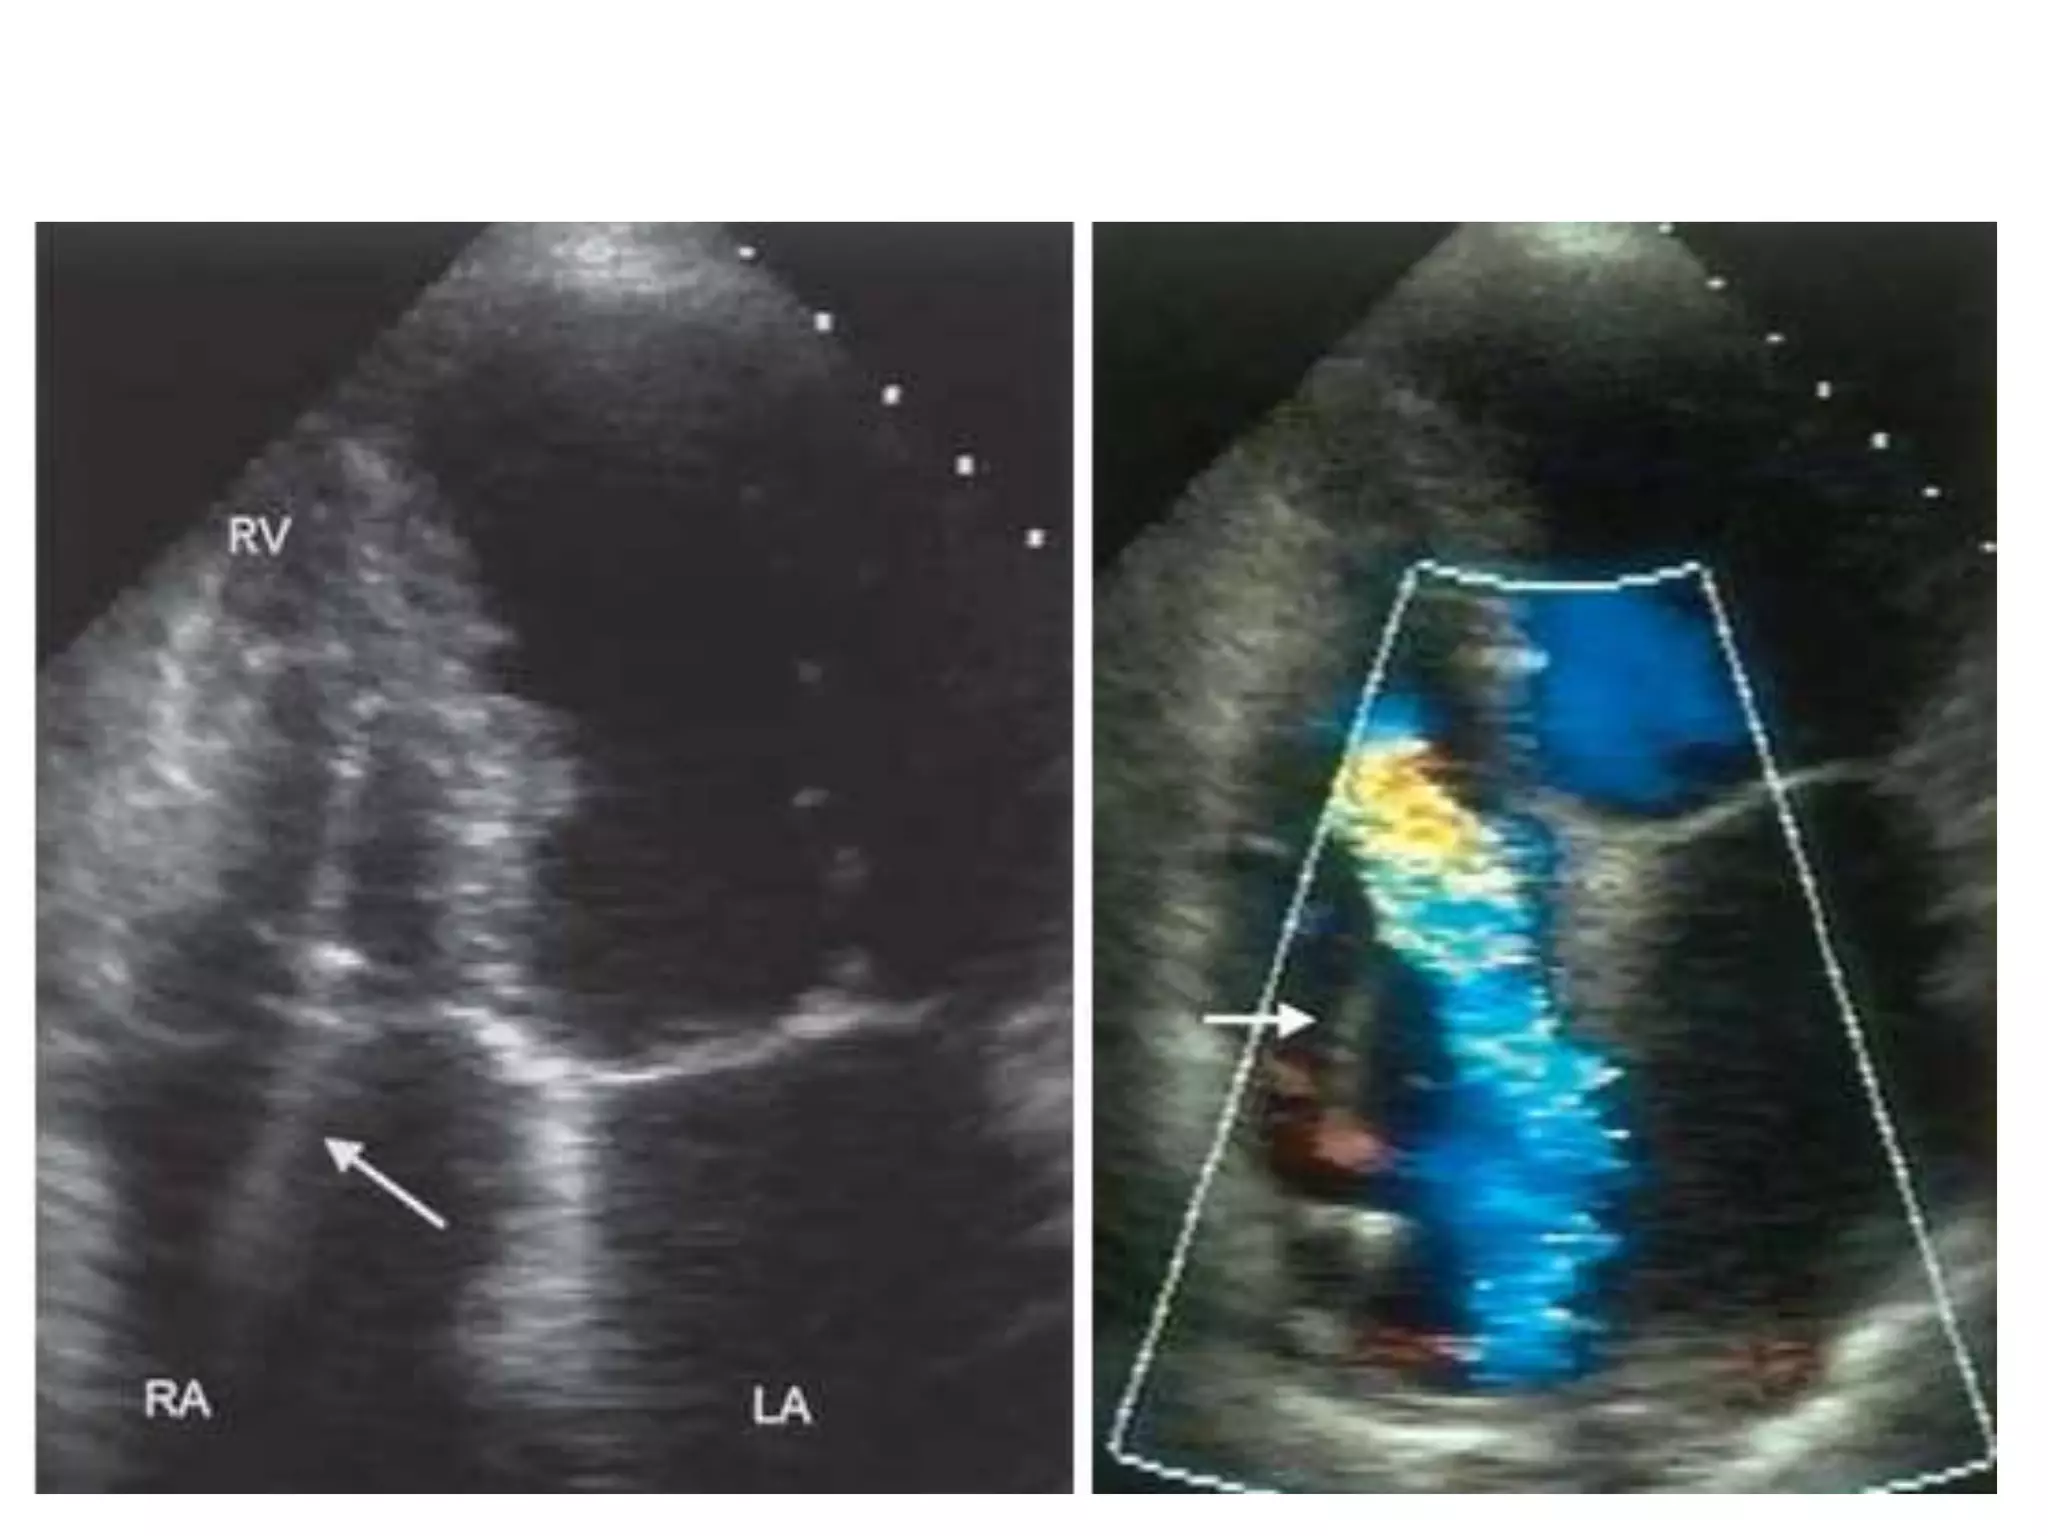

TR

• 2-D echo –Dilated PA (e.g. parasternal short-axis view at aortic level). The PA diameter should normally not be greater than aortic diameter – RV dilatation and/or hypertrophy – RA dilatation – Abnormal IVS motion – Underlying cause, e.g. MV or AV disease, ASD, VSD, LV dysfunction. • Doppler – This is the best method to assess PA systolic pressure using TR velocity (as described in Ch. 3), or short PA acceleration time as a surrogate of PHT.